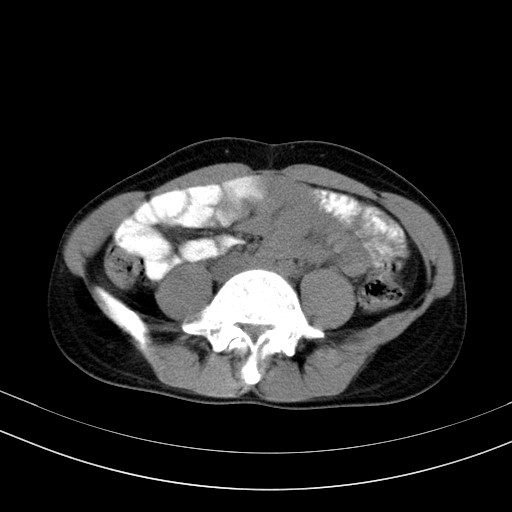

以下是引用随光逐影在2009-4-7 8:17:00的发言:[br]考虑宫颈占位性病变(宫颈癌?);建议行进一步检查。

以下是引用jiangjing在2009-4-7 16:46:00的发言:[br]宫颈增大,结构不清,右侧附件区可疑囊样占位,建议增强及mri 检查